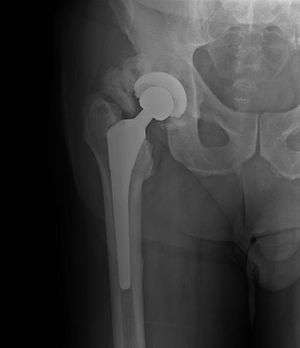

| Heterotopic ossification around the hip joint in a patient who has undergone hip arthroplasty | |

Heterotopic ossification of varying severity can be caused by surgery or trauma to the hips and legs. About every third patient who has total hip arthroplasty (joint replacement) or a severe fracture of the long bones of the lower leg will develop heterotopic ossification, but is uncommonly symptomatic. Between 50% and 90% of patients who developed heterotopic ossification following a previous hip arthroplasty will develop additional heterotopic ossification.